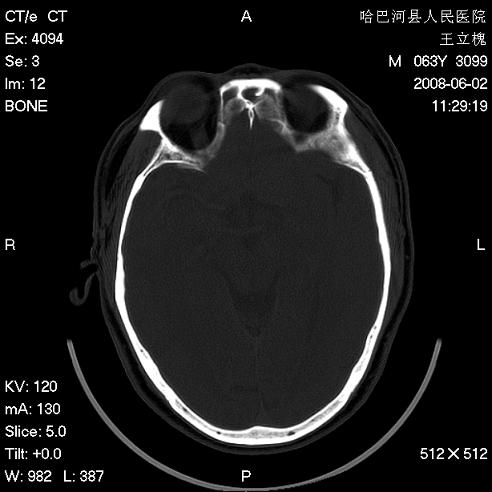

标题: CT13803:反复性鼻塞、流涕一年余 [打印本页]

标题: CT13803:反复性鼻塞、流涕一年余

副鼻窦炎,右上额窦积脓。左眼肌锥内见致密影,视神經受压

1.全组副鼻窦炎2.双侧上颌窦积液

全组副鼻窦炎 肌锥内高密度灶。建议进一步检察检查

2、左眼眶肌锥内病变,小血管瘤?建议增强。

1)全副鼻窦炎(左侧上颌窦黏膜下囊肿或息肉)。2)左眼眶肌锥内不规则小结节状软组织密度影;考虑为小血管瘤可能。建议行ct增强扫描检查。

全组副鼻窦炎,左侧肌锥内不规则形软组织肿块影,与眼外肌密度相当,左侧视神经受压,肿块与视神经及眼外肌分界清晰,眼外肌无增粗,眶壁无破坏,球后脂肪间隙不模糊,考虑良性改变,小血管瘤或神经源性肿瘤可能,建议增强扫描。

谢谢,增强扫描做了,眶内病灶与海绵窦同步明显强化,血管瘤